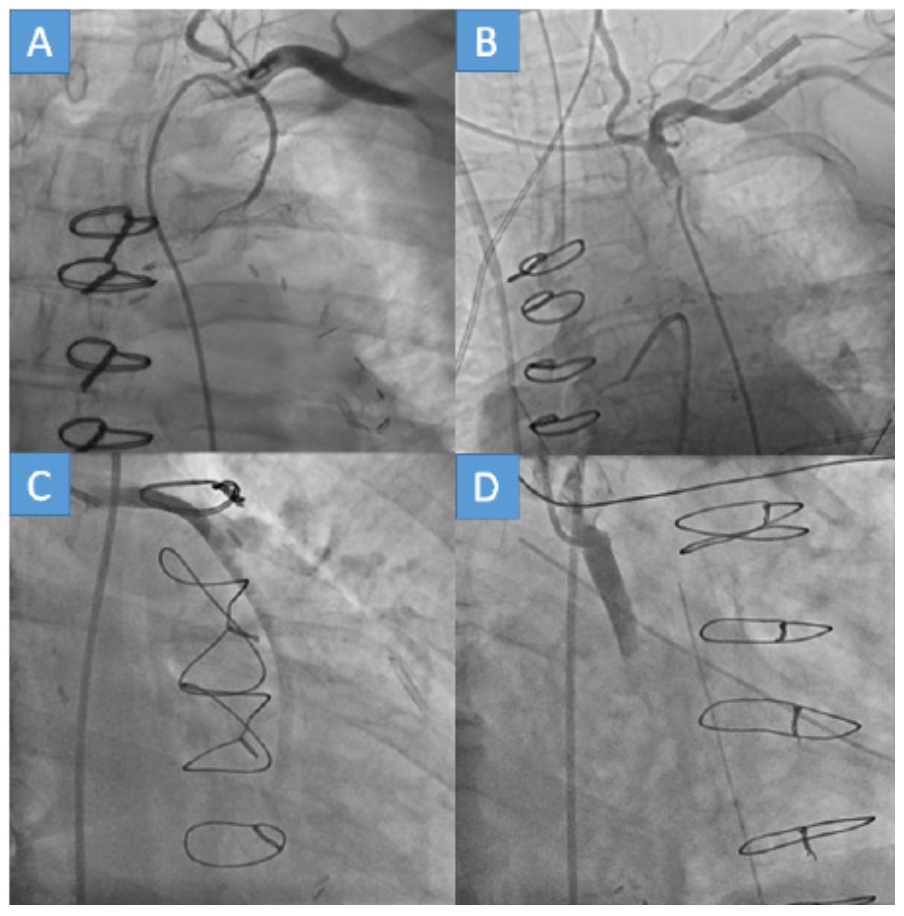

The incidence of complete graft occlusion was similar across graft types: LIMA (18%), RIMA (25%), non-sequential SVG (19%), and sequential SVG (18%) (P=.54). However, the incidence of partial graft occlusion was higher in non-sequential SVG (41%) compared with LIMA (26%), sequential SVG (23%), and RIMA (17%) (P<.01). Complete occlusion of at least 1 bypass graft was observed in 35 patients (32%) and all bypass grafts were patent in 36 patients (32%). The findings of the coronary angiographies are demonstrated in Figure 3 and Figure 4.